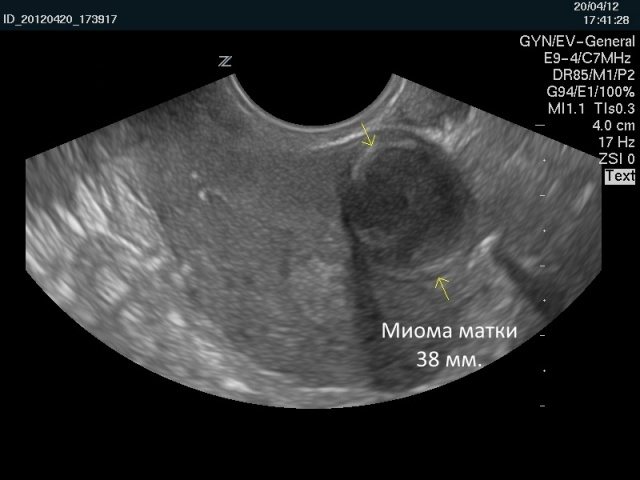

• УЗИ органов малого таза. Во время этого исследования визуализируются изменения, указывающие на миому матки.